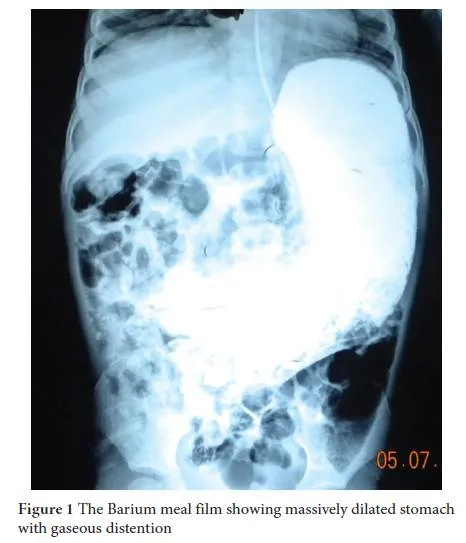

- Barium meal: Dilated stomach, delayed emptying.